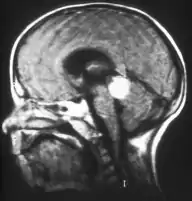

Inherited forms of retinoblastomas are more likely to be bilateral. In addition, inherited uni- or bilateral retinoblastomas may be associated with pineoblastoma and other malignant midline supratentorial primitive neuroectodermal tumors (PNETs) with a dismal outcome; retinoblastoma concurrent with a PNET is known as trilateral retinoblastoma.[13] A 2014 meta-analysis showed that 5-year survival of trilateral retinoblastoma increased from 6% before 1995 to 57% by 2014, attributed to early detection and improved chemotherapy.[14]

Traditional ultrasound B scan can detect calcifications in the tumour while high-frequency ultrasound B scan is able to provide higher resolution than the traditional ultrasound and determine the proximity of the tumour with front portion of the eye. MRI scan can detect high-risk features such as optic nerve invasion; choroidal invasion, scleral invasion, and intracranial invasion. CT scan is generally avoided because radiation can stimulate the formation of more eye tumours in those with RB1 genetic mutation.[24]

Aspect of trilateral retinoblastoma on MRI